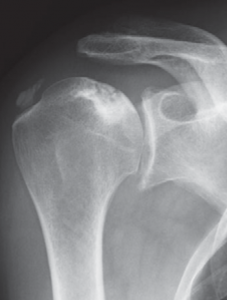

Der klassische Verschleiß des Schultergelenkes tritt im Vergleich zum Hüft- und Kniegelenk beim älteren Menschen seltener auf. Hierbei erfolgen eine Zerstörung des Gelenkknorpels und die Deformierung der Gelenkflächen, die zu einer schmerzhaften Bewegungseinschränkung des Schultergelenkes führen (Abb. 34, 37).